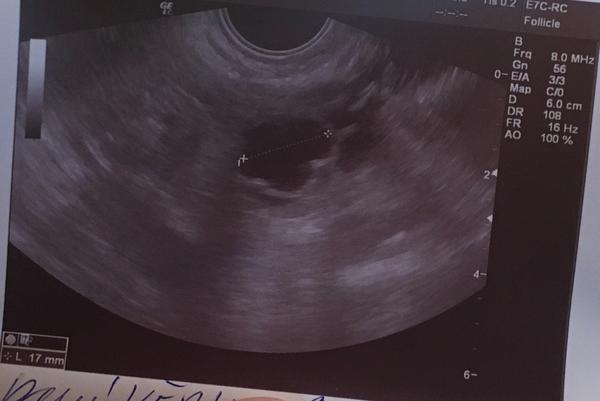

@vandand pokud je to fotka cysty,tak je jeji okraj dost nepravidelny (folikul je takovy cistejsi linie)..jen mi neni jasna ta sliznice,to na mestruaci jen tak nevypada,je prilis nizka...

@vandand A ses si jista, ze rikal 1,8 cm dlouha cysta? Folikul totiz kdyz v tech 2,5 cm nepraskne tak se zvetsuje dal a vznikne z nej cysta. Ten obrazek tam ma napsano 6cm.. jako D, to predpokladam, ze je delka, ta teckovana cara to meri. Vypada na cystu 6cm bych rekla.. Ano a folikul je vetsinou kulaty myslim. Vse jen dohady, nejsem doktor..

@vandand Mám jen osobní zkušenost. Folikul mi dorostl až na 26mm, myslím, že pokud bych neměla ten cyklus ovitrelle, nepraskl by. Folikul vidím na utz vždycky černou barvou, pevně ohraničený a kulatý. Cystu jsem měla 2x, vždy 3cm, kulatou a na utz byla jakoby šrafovaná, šedá (ale vím, že tu psaly holky, že ony ji měly černou).

@jednaholkaa no vlevo dole vypadá jak znak toho zaměření a je tam 17mm, to bych spis tipla na tu délku. To D jsem si rikala jestli není spis výška sliznice. Nevím, uvidím. Každopádně jsem měla typickej ovulacni hlen, tak čekám na MS a raději zkouším i ovulacni test 😀 znama doktorka mi řekla ze by 1,8 nenazvala jako cystu ale ze je těžký soudit z jednoho obrázku a nevidět cely utz.

@vandand A jo, vidim dole..17mm. Tak to D bude neco jinyho..

Folikul je ovalny tvar s ostrymi rysy a nebyva vetsi nez 23-25mm (to uz pak praskne)..mne cystu oznacili utvar vetsi 30mm